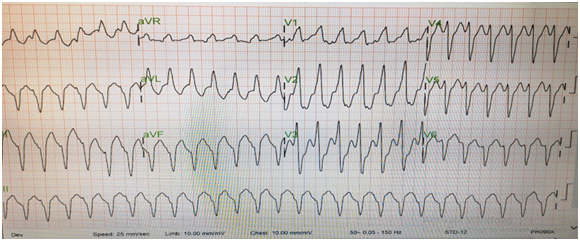

This is 34-year-old male patient presented to our hospital with 2 days history of dizziness and myalgia. Initially he denied any past medical illnesses. He is working at a company in the desert. Up on arrival his BP was 80/50, HR 160/min, ECG showed monomorphic ventricular tachycardia (Figure 1). While preparing for cardioversion, he received adenosine 6mg then 12 mg IV, then IV 150 mg of amiodarone but no response noted. He was sedated and first cardioversion was given. His rhythm converted to sinus (Figure 2). Due to the hypotension, he was resuscitated with IV normal saline. Then he developed dyspnea and desaturated in room air, required intubation and ventilation. He was put on amiodarone infusion. His initial work up showed the following Table 1.

Figure 1 ECG: Monomorphic ventricular Tachycardia